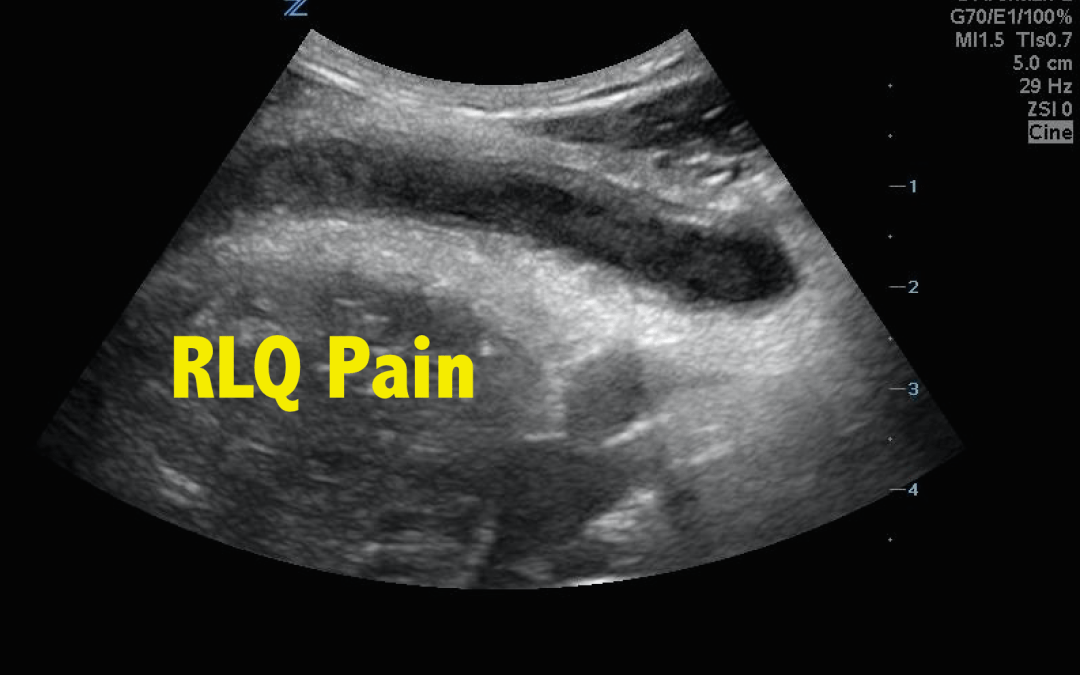

A 27-year-old male with no significant PMH presented to the ED with complaints of RLQ abdominal pain that had been ongoing for 11 hours. He also reported nausea, vomiting, diarrhea, anorexia, and fever. Initial VS: BP 109/58, HR 94, T 38.5 °C (101.3 °F), RR 12,...